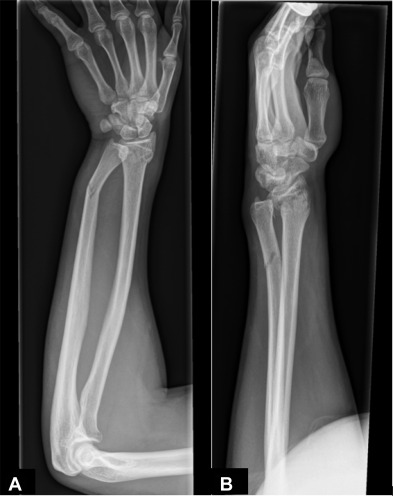

- Fractures

- Types of Fractures – oblique, simple, comminuted, open, pathologic, segmented, spiral, transverse, greenstick, impacted, Colles fracture, Pott’s fracture, compression fracture of vertebra, avulsion, stress (fatigue or insufficiency),

- Treatments: reduction/realignment of fracture ends, casts, pins, wires, plates, sarcoplasty, bone grafts, intramedullary nail, electrical stimulation, ultrasound stimulation